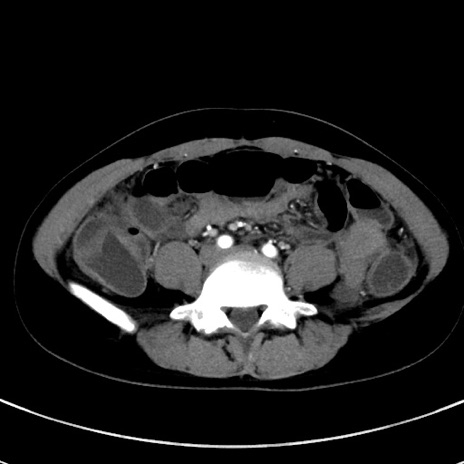

症例17(横断像)

【症例】20歳代女性

【主訴】嘔吐、下腹部痛

【現病歴】昨日夕食後に嘔吐し下腹部痛が出現。本日になっても嘔吐持続し改善しないため来院。

【身体所見】意識清明、BT 37.2℃、BP 108/67mmHg、腹部:平坦、やや硬、下腹部正中から右にかけて圧痛あり、反跳痛軽度あり、tapping pain(+)。

【データ】WBC 13600、CRP 14.94